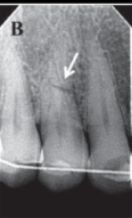

Vertical Root Fracture

Fracture that runs vertically along the length of the root.

Vertical Fracture Identification

Detection based on characteristic patterns in radiographs.

horizontal root fracture

vertical fracture

not always visualized but shows j shape lucency